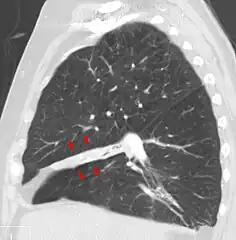

Atelectasis of a person's right lung

Atelectasis is the collapse or closure of a lung resulting in reduced or absent gas exchange. It is usually unilateral, affecting part or all of one lung.[2] It is a condition where the alveoli are deflated down to little or no volume, as distinct from pulmonary consolidation, in which they are filled with liquid. It is often called a collapsed lung, although that term may also refer to pneumothorax.[1]

Clinically significant atelectasis is generally visible on chest X-ray; findings can include lung opacification and/or loss of lung volume. Post-surgical atelectasis will be bibasal in pattern. Chest CT or bronchoscopy may be necessary if the cause of atelectasis is not clinically apparent. Direct signs of atelectasis include displacement of interlobar fissures and mobile structures within the thorax, overinflation of the unaffected ipsilateral lobe or contralateral lung, and opacification of the collapsed lobe. In addition to clinically significant findings on chest X-rays, patients may present with indirect signs and symptoms such as elevation of the diaphragm, shifting of the trachea, heart and mediastinum; displacement of the hilus and shifting granulomas.[10]